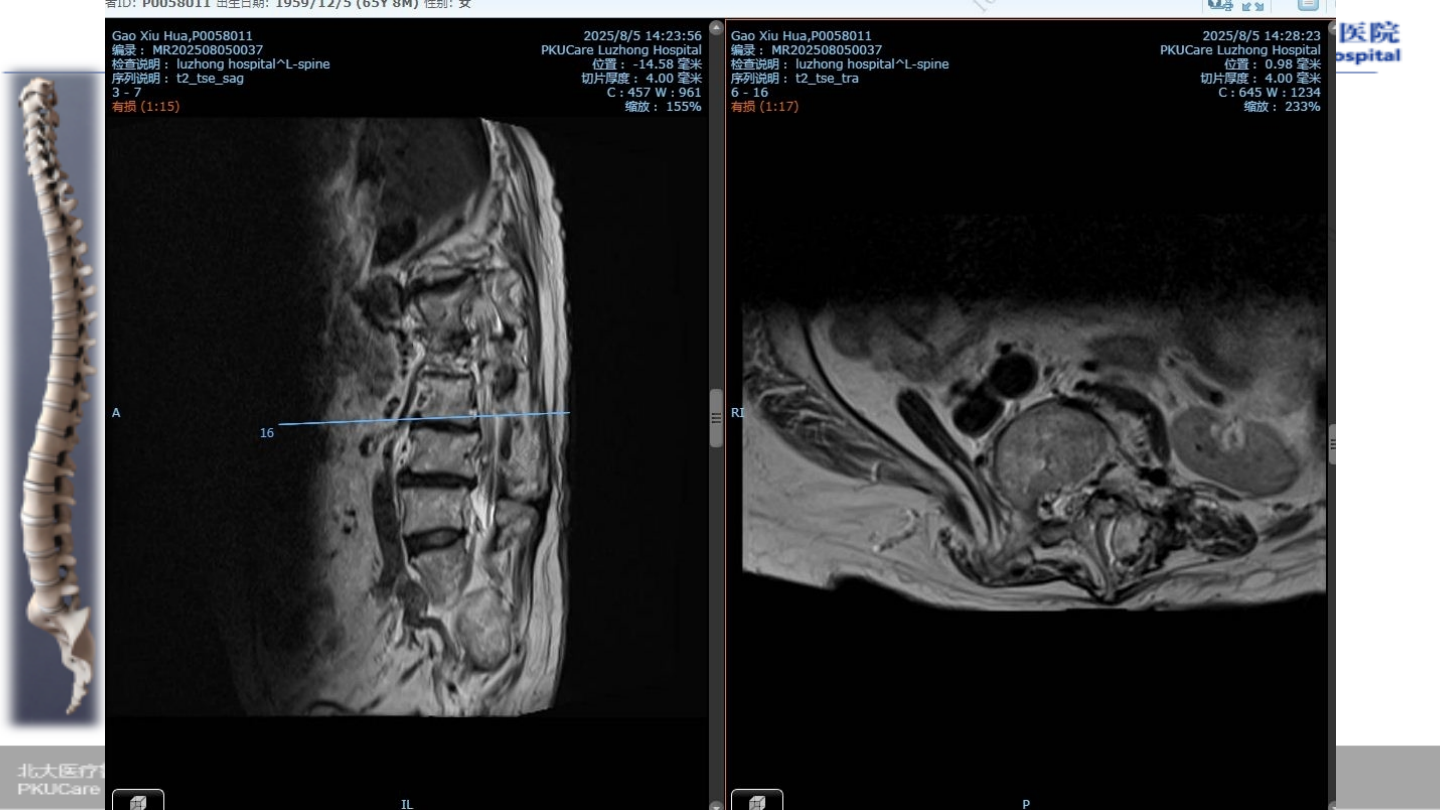

u

患者:高某,女性,

65

主诉:

腰疼伴行走困难,双下肢麻木

1

症状:腰部疼痛,双下肢行走困难,双下

肢小腿外侧疼痛麻木

.

Oswestry

功能障碍指数(

ODI

):

85%

VAS:8

病例

2

术前

MRI